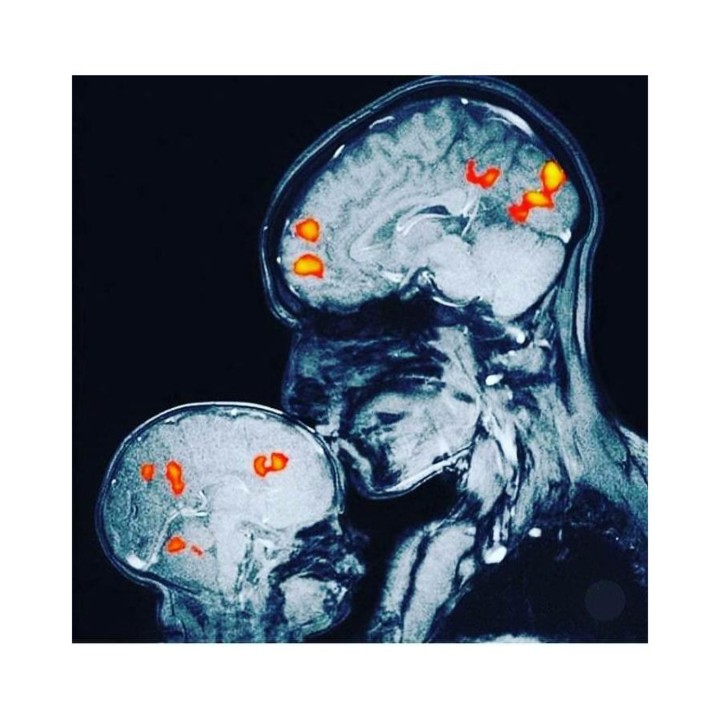

Imagem: ressonância magnética mostrando como um beijo entre mãe e filho pode desencadear uma reação no cérebro: a libertação de oxitocina, a hormona do afeto, empatia e amor.